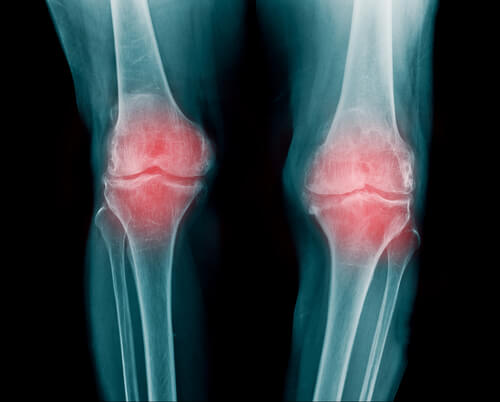

Une articulation est une zone où se rejoignent les extrémités de deux os, ou bien d’un os et d’un cartilage. Grâce aux articulations, le corps peut bouger ; elles permettent ainsi aux jambes, aux bras et au dos de fléchir et de tourner.

Entre les os qui forment l’articulation se trouve un tissu élastique et flexible : le cartilage articulaire. Il empêche le frottement entre les os en agissant comme système amortisseur.

L’articulation est entourée d’une capsule articulaire qui protège tout le système. Des ligaments renforcent cette capsule et empêchent les articulations de s’endommager facilement.

- C’est une inflammation de l’articulation qui peut apparaître dans différentes zones : les doigts, les bras et les genoux sont généralement les plus touchés.